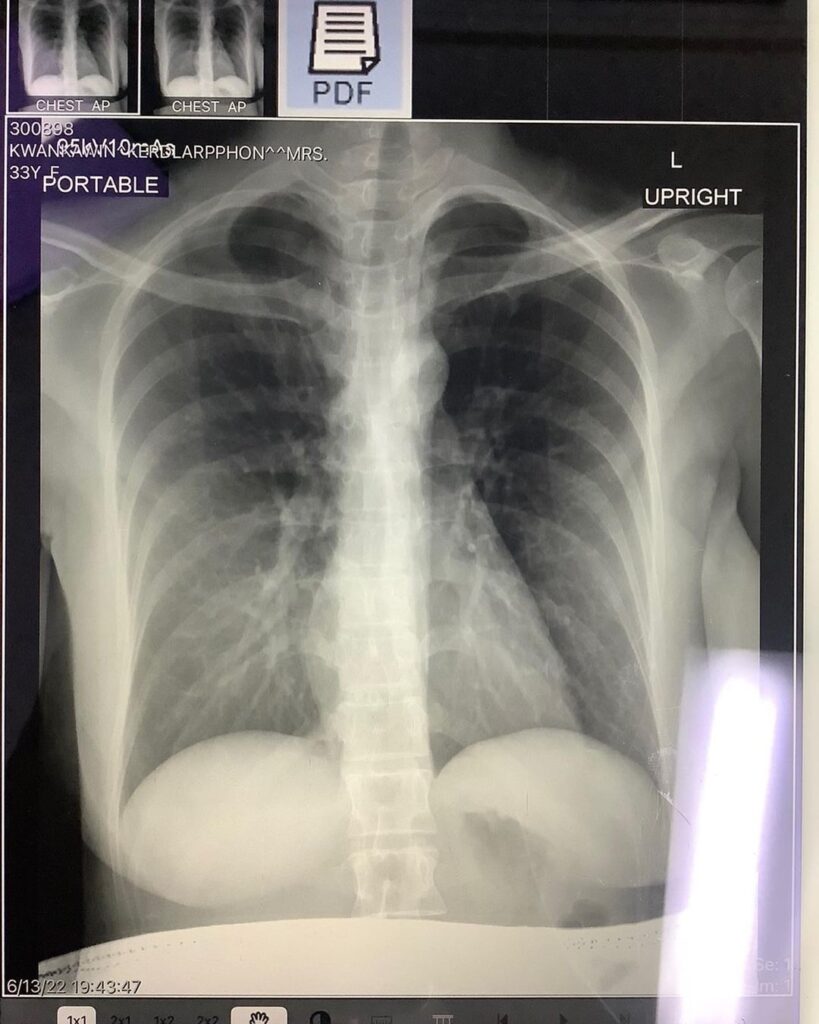

วันนี้วันที่ 4 แล้ว อาการค่อยๆดีขึ้นตามลำดับ ปอดยังปกติดี แม่ท้องท่านอื่นที่ติดโควิด แม้ไม่ได้รับยาต้าน แต่คุณหมอแจ้งว่าไม่ต้องกังวล อาการจะค่อยๆดีขึ้นเอง เอกซเรย์ปอดได้ถ้าจำเป็น แต่ต้องมีแผ่นตะกั่วปิดท้องให้น้องด้วยนะคะ

👶🏻สงสารลูกจัง แม่ไอทีนึงสะเทือนทั้งตัว หลังจากนี้จะดูแลตัวเองให้ดีมากๆ ขอบคุณทุกกำลังใจนะคะ ขอบคุณรพ. รามคำแหงที่ดูแลดีมากๆค่ะ คุณหมอบอกว่าช่วงนี้กลับมาเป็นกันเยอะขึ้นมาก ดูแลตัวเองด้วยน้าาทุกคน💗